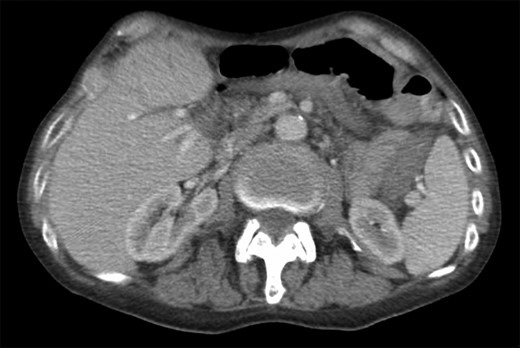

Initial inpatient evaluation started with pan endoscopy. Upper endoscopy demonstrated a Billroth II anastomosis with patent efferent and afferent limbs and no evidence of marginal ulceration or malignancy. Colonoscopy, likewise, was unremarkable. Radiographic evaluation with computed tomography of the abdomen and pelvis did not show evidence of pancreatic tumor or biliary ductal dilatation (Fig. 1). An octreotide scan, however, demonstrated increased activity near the head of the pancreas and abdominal aorta (Fig. 2 a-b). Endoscopic ultrasound did not fully evaluate the head of pancreas but showed no lesions in the left lobe of the liver, pancreatic body and tail. Capsule endoscopy then followed and was unremarkable. Despite being placed nil per Os, the patient’s diarrheal symptoms and hypokalemia persisted. Stool cultures obtained on admission demonstrated no growth.

Computed tomography scan of the abdomen and pelvis with intravenous contrast (Omnipaque 350TM, iohexol, 50 mL). No evidence of pancreatic mass or biliary ductal dilation was identified.